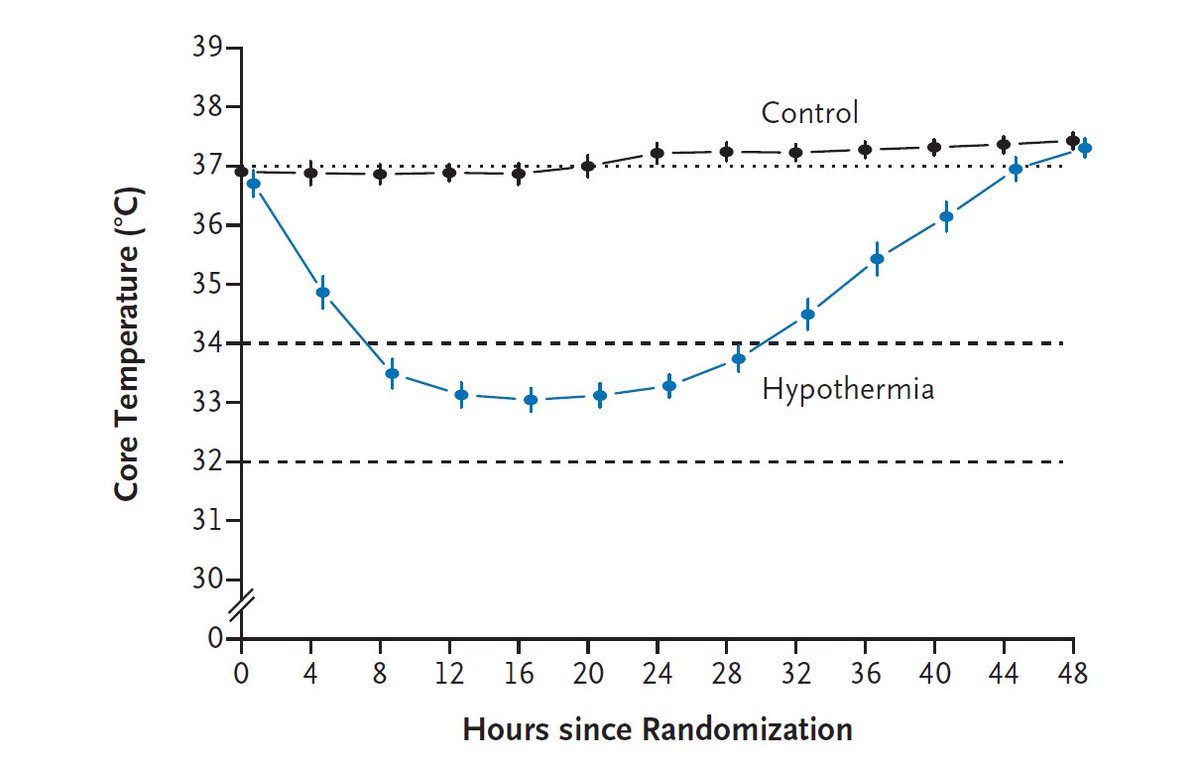

Original Article: Hypothermia for Neuroprotection in Convulsive Status Epilepticus http://nej.md/2h06pru pic.twitter.com/y6Cg60GkbR